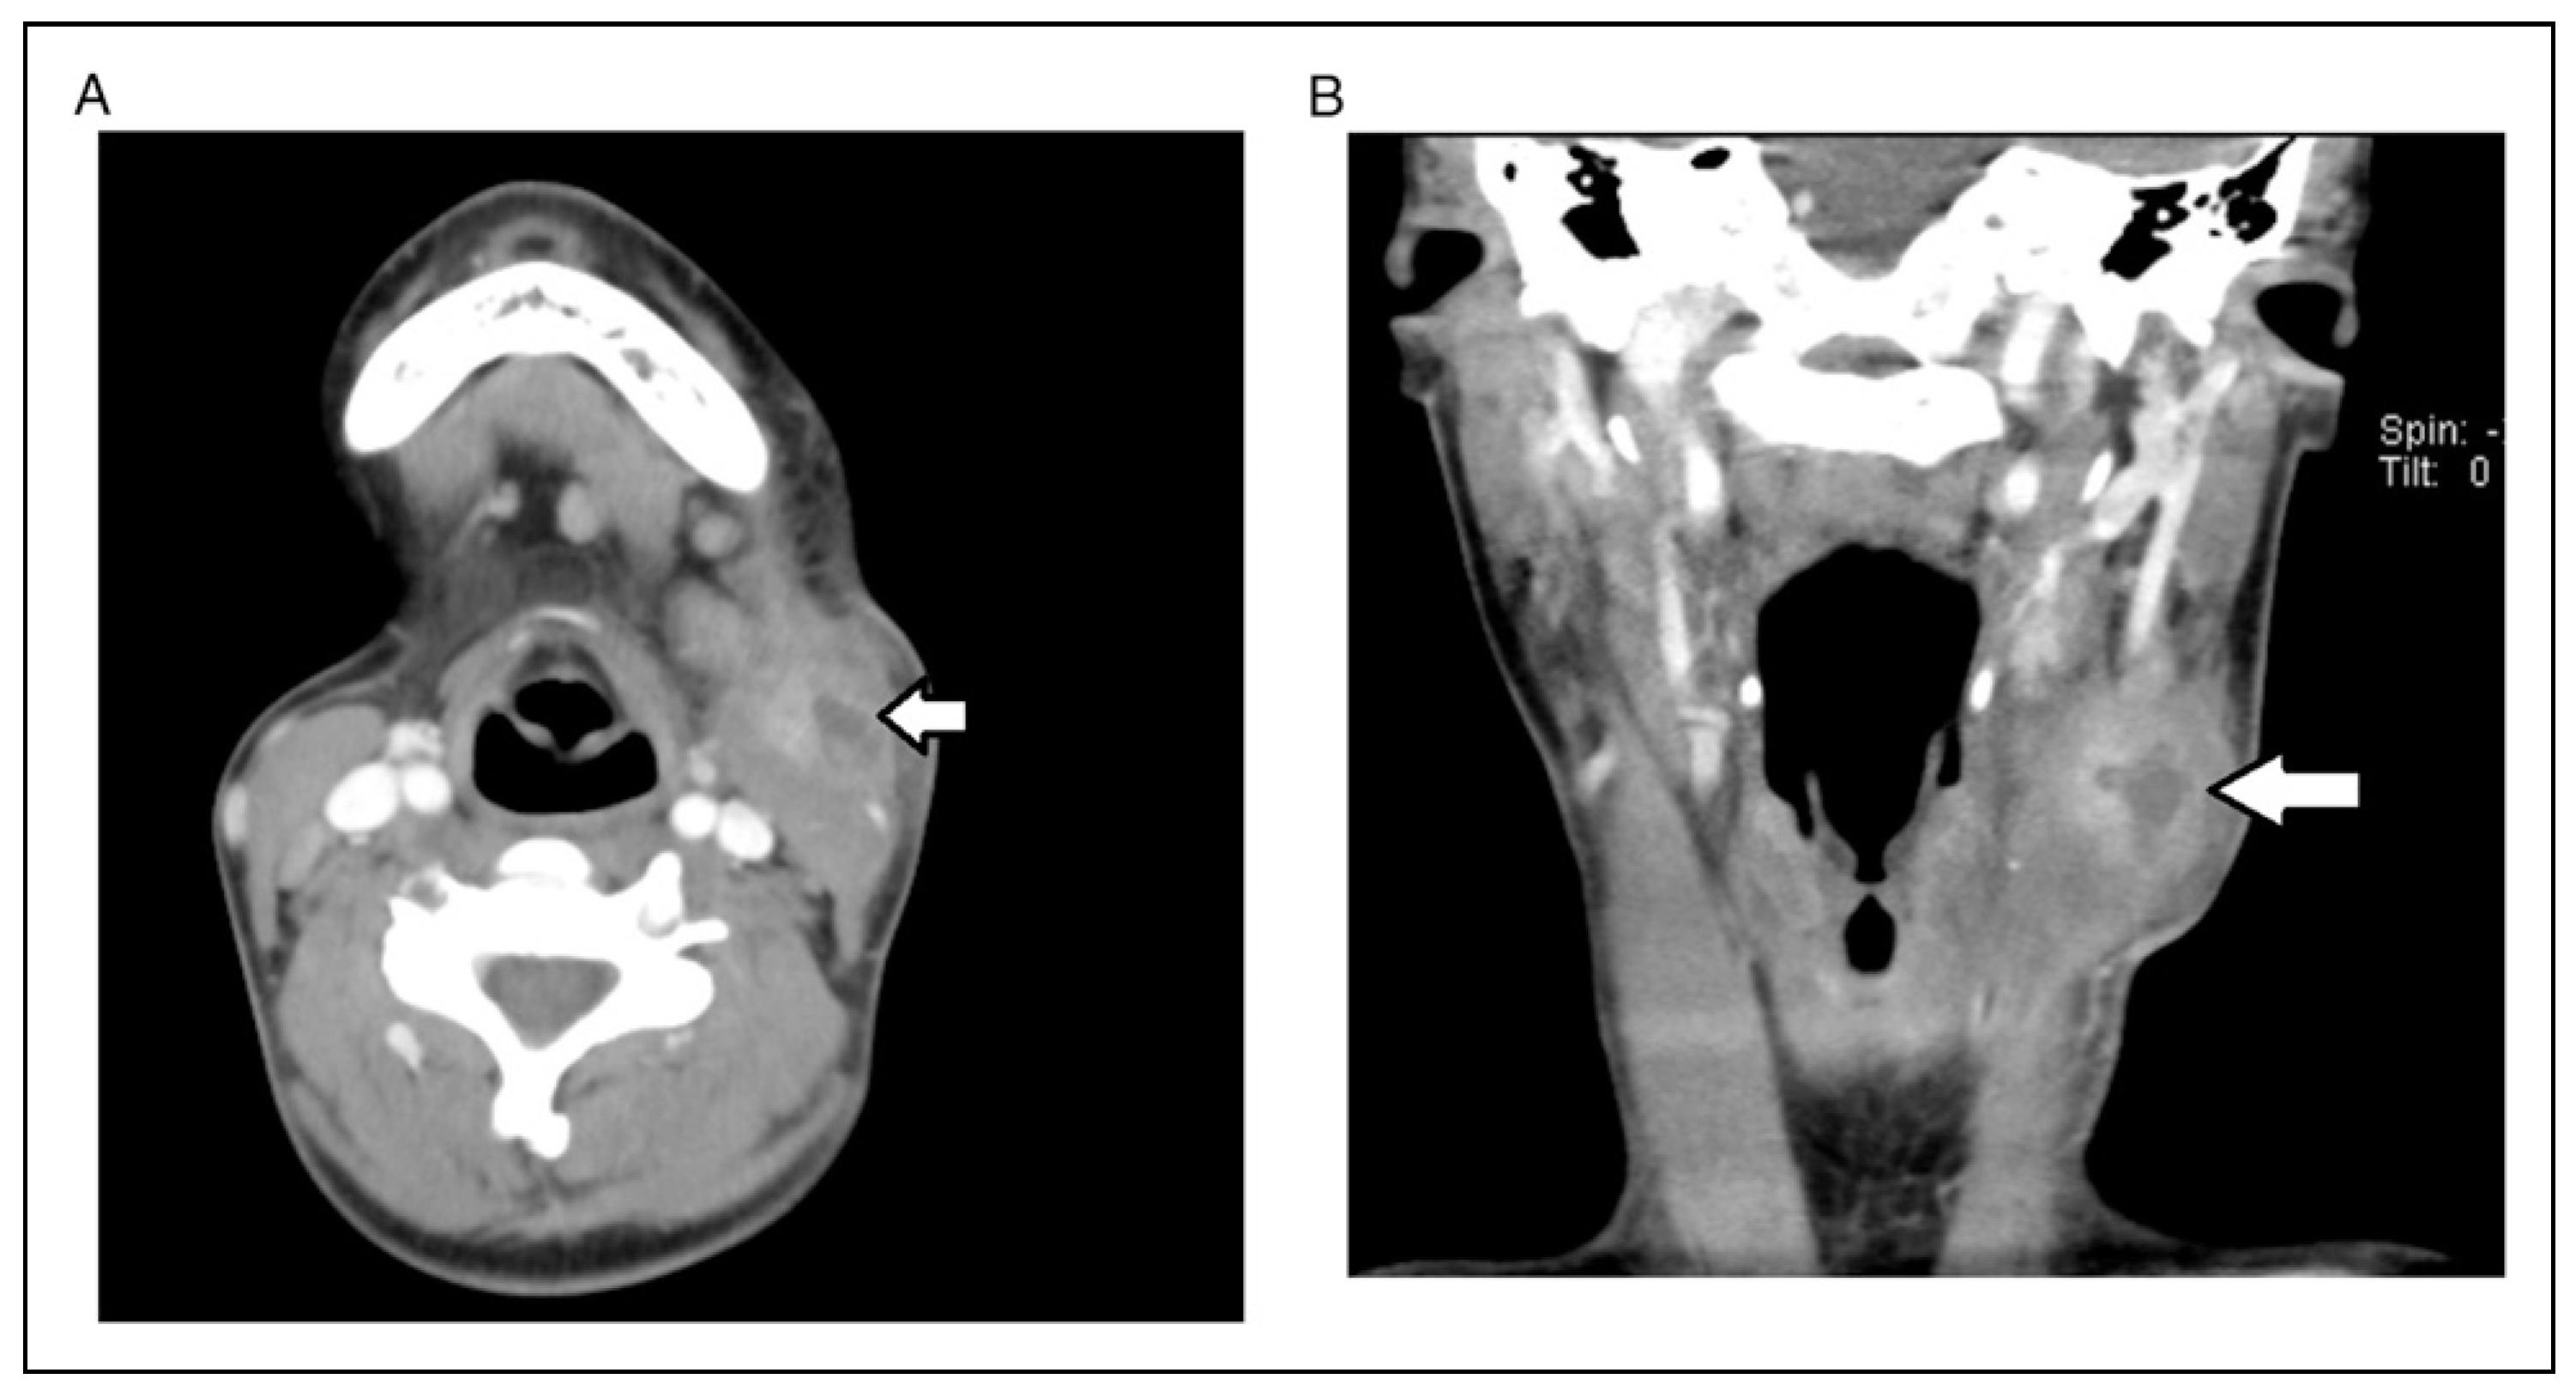

A 17-year-old woman presented for evaluation and treatment of mandibular hypoplasia (Figure 1A and 1B). Her medical history was significant for type I diabetes mellitus with an A1C of 8.1 one week prior to surgery. Her only prior surgery was tonsillectomy as a young child from which she recovered without issue. Her social history of negative for tobacco, alcohol, and drug use (smoking, vaping, use of tobacco of any kind). She received 1 g of cefazolin prior to incision. A bilateral sagittal split osteotomy (BSSO) was performed without intraoperative complication. Her lower third molars were not visualized during the surgery and were left in place. It was felt that removing them would lead to an unplanned fracture of the distal segment and that they would be removed at a later date. The mandible was fixed with a single 4-hole mono-cortical miniplate as well as 1 posterior bicortical screw bilaterally (Figure 2A and 2B). Her postoperative course was benign. She was admitted for 23-h observation during which time she received 2 doses of 3 g of Unasyn. She tolerated a clear liquid diet; postoperative radiographs were obtained (Figure 2A and 2B).

Four months after surgery, she presented with pain and fluctuance noted intraorally in the left mandibular vestibule. An incision and drainage was performed in the clinic under local anesthesia. Purulence expressed from the wound and was cultured. (Cultures were positive for normal oral flora. Actinomycosis was not seen.) The patient was given a 1-week course of Augmentin. The patient followed up a week later and was improving but her swelling and pain were not completely resolved. She was prescribed an additional week of Augmentin. She had resolution of symptoms when seen for follow up 3 weeks after her initial onset of symptoms. However, slightly over 1 month later (5 months after her BSSO) the patient re-presented with painful swelling on her left neck. Specifically, the swelling was along the anterior border of the SCM. In addition, she had a firm swelling along her left mandibular body. On examination, she was tender and warm over both sites, but these was no change in color to the skin. It was thought to be possible that she had a reactive or necrotic lymph node along her SCM. She was started on Bactrim as the previous intraoral culture taken grew Staphylococcus Aureus that was penicillin resistant but oxacillin sensitive. Three days later her symptoms and swelling had markedly increased prompting the need for hospitalization (Figure 3).

On admission her WBC was 6.6 and her A1C was 7.9 She was started on Unasyn without resolution or worsening of symptoms. CT of the neck with contrast showed a multiloculated abscess superficial to the SCM muscle as well as an abscess superficial to the mylohyoid muscle in the left submandibular region. Interventional radiology was consulted to see if they could aspirate the lesion to get a culture. They performed an ultrasound guided aspiration of the lesion; however, no growth resulted from their aspirate. Clinically, there was minimal change in her findings.

Figure 3. A, B Axial and coronal images showing as abscess associated with superficial aspect of the SCM 5 months after surgery.